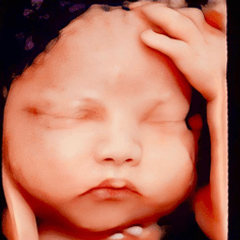

Siêu âm 4D là kỹ thuật chẩn đoán hình ảnh giúp mẹ bầu quan sát trực tiếp hình ảnh và hoạt động của thai nhi trong bụng mẹ. Hình thức siêu âm này mang đến xúc cảm chân thực cho ba mẹ vì cảm giác như con đang ở ngay cạnh mình vậy✅ Siêu âm 4D còn giúp phát hiện các dị tật bẩm sinh như hội chứng Down, sứt môi, hở hàm ếch, hoặc các bất thường về tay, chân, ngón tay, ngón chân để bác sĩ kịp thời tư vấn. Website: https://drhoasieuam.com/thoi-diem-nao-thich-hop-de-sieu-am-4d/ Địa chỉ: Shop 02 chung cư Mỹ Phú, 60/68 Lâm Văn Bền, Phường Tân Kiểng, Quận 7, TP HCM. Hotline: 0907768037